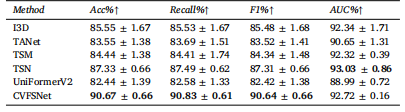

Table 4Quantitative comparison of the scoring performance of different methods on AmTICIS. † indicates significancy (𝜌 < 0.05). Best results are indicated in bold.

表4:在自动改良脑梗死溶栓分级评分(AmTICIS)数据集上,不同方法的评分性能的定量比较。†表示具有显著性((\rho < 0.05))。最优结果以粗体显示。

We proposed a CVFSNet based on dual-view angiographic imagesfor automatic, objective, end-to-end mTICI scoring and built a crossview fusion module, CVFM, to integrate, aggregate, and complementfeatures from different views. In the ablation experiments, we firstcompared the performance between single-view and dual-view inputs,demonstrating the necessity of dual-view image input. This may bedue to the fact that DSA imaging is projection-compressed and intracranial vessel structures are complex, leading to vessel overlap insingle-view images, which affects the model’s ability to characterizeblood flow accurately. Then, by comparing different methods of dualview feature fusion, we verified the effectiveness of the CVFM module.CVFM leverages prior positional knowledge of coronal and sagittalviews, constructs oblique sagittal features using trigonometric functionsand the Pythagorean theorem, and employs a transformer-like moduleto explore complementary relationships between coronal and sagittalfeatures, thereby building global dependencies and generating more expressive fused features, ultimately enhancing performance. In the comparative experiments, we compared our approach with some classicaland state-of-the-art video feature classification models, demonstratingsuperior performance andgood stability.In the dichotomized experiments, CVFSNet demonstrated performance exceeding 90% across all indicators, implying that CVFSNet mayhave the potential for clinical application in determining the adequacyof mTICI scores. However, our study also has limitations. Firstly, thesevideo feature classification methods that were compared in the comparative experiments only supported single-view inputs, which maydisadvantage their comparison in terms of performance. Additionally,the AmTICIS dataset constructed in this study only includes data forM1 segment stenosis, limiting its clinical applicability. In the future,we plan to expand the dataset to include more mTICI scoring datawith various vessel stenosis, such as Internal Carotid Artery (ICA), BaseArtery (BA), Anterior Cerebral Artery (ACA), and Posterior CerebralArtery (PCA) etc., thereby constructing a more comprehensive scoringdataset. Also, the sample size of AmTICIS can be further expanded byincorporating data from multiple centers to enhance its diversity.In conclusion, we propose a novel CVFSNet in this paper for automatic, objective, and end-to-end mTICI scoring. Specifically, CVFSNetemploys dual branches to simultaneously extract spatial–temporal features from coronal view and sagittal view, and these cross-view featuresare fused through a novel cross view fusion module that explores thepositional characteristics of coronal and sagittal views to fuse andgenerate a pseudo-oblique sagittal feature and deploys a transformerlike architecture to explore the correlation between different viewfeatures, ultimately constructing more representative features to enhance the scoring performance of the model. In addition, we providea newly collected and the first publicly available digital subtractionangiography image dataset with expert annotations (AmTICIS) for automatic mTICI scoring, which can effectively promote researchers toconduct studies of ischemic stroke based on DSA images and finallyhelp patients get better medical treatment. Extensive experimentationresults demonstrate the promising performance of our methods and theeffectiveness of the cross-view fusion module.

我们基于双视角血管造影图像提出了CVFSNet网络,用于实现自动、客观、端到端的脑梗死溶栓治疗改良分级(mTICI)评分,并构建了一个跨视角融合模块(CVFM),以整合、聚合和补充来自不同视角的特征。在消融实验中,我们首先比较了单视角输入和双视角输入的性能,结果表明了双视角图像输入的必要性。这可能是因为数字减影血管造影(DSA)成像是投影压缩的,且颅内血管结构复杂,导致单视角图像中出现血管重叠,从而影响了模型准确表征血流的能力。然后,通过比较不同的双视角特征融合方法,我们验证了CVFM模块的有效性。CVFM利用冠状面和矢状面的先验位置知识,使用三角函数和勾股定理构建斜矢状面特征,并采用类似Transformer的模块来探索冠状面和矢状面特征之间的互补关系,从而建立全局依赖关系,并生成更具表现力的融合特征,最终提升性能。在对比实验中,我们将我们的方法与一些经典的以及最先进的视频特征分类模型进行了比较,结果显示出我们的方法具有优越的性能和良好的稳定性。 在二分类实验中,CVFSNet在所有指标上的表现均超过了90%,这意味着CVFSNet在确定mTICI评分是否足够方面可能具有临床应用潜力。然而,我们的研究也存在局限性。首先,在对比实验中所比较的这些视频特征分类方法仅支持单视角输入,这在性能比较方面可能对它们不利。此外,本研究构建的AmTICIS数据集仅包含大脑中动脉M1段狭窄的数据,限制了其临床适用性。未来,我们计划扩展该数据集,纳入更多具有各种血管狭窄情况的mTICI评分数据,例如颈内动脉(ICA)、基底动脉(BA)、大脑前动脉(ACA)和大脑后动脉(PCA)等,从而构建一个更全面的评分数据集。同时,通过纳入多个中心的数据来进一步扩大AmTICIS的样本量,以提高其多样性。 总之,本文提出了一种新颖的CVFSNet网络,用于自动、客观、端到端的mTICI评分。具体而言,CVFSNet采用双分支同时从冠状面和矢状面提取时空特征,并且这些跨视角特征通过一个新颖的跨视角融合模块进行融合。该模块探索冠状面和矢状面的位置特征,以融合并生成伪斜矢状面特征,并部署了类似Transformer的架构来探索不同视角特征之间的相关性,最终构建出更具代表性的特征,以提升模型的评分性能。此外,我们提供了一个新收集的、首个带有专家注释的公开可用的数字减影血管造影图像数据集(AmTICIS),用于自动mTICI评分,这可以有效地推动研究人员基于DSA图像开展缺血性中风的研究,并最终帮助患者获得更好的治疗。大量的实验结果证明了我们方法的良好性能以及跨视角融合模块的有效性。